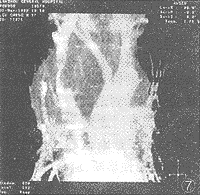

2.1.7 纵隔恶性畸胎瘤上腔静脉受累1例,表现中上纵隔巨大混杂密度(脂肪、软组织及钙化),上腔静脉僵硬变窄(图7)。其轴位像显示右侧胸壁浅表静脉曲张,而CTA成像选择感兴趣范围时被删减。

图7 3D-Angio像,纵隔恶性畸胎瘤上腔静脉受累